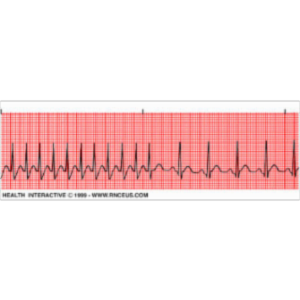

This learning module consists of 6 cardiac case studies.  Each case study is followed by 5 questions over the material and provides instant feedback for answers.  It includes an optional 30 question exam and the opportunity to provide feedback on the quality of the course. The learning module would be helpful to nursing students who are reviewing information on cardiac conditions and the associated cardiac arrhythmias.It is available...

This drill and practice material is well laid out. The table of contents makes it very easy to navigate the page. The content is accurate, appropriate and relevant to patient care. There is also relevance to curriculum content in nursing education since each nurse must be aware on cardiac conditions, be able to read EKG strips and provide nursing evaluation and management for patients with cardiac conditions. Recognizing various EKGs is a difficult topic which requires practice therefore, I was quite pleased to note that the page also provides another link to course material where student nurses can acquired knowledge on the topic while, registered nurses can take the course to acquire continuing nursing education credits towards the renewal of their licenses. Due to the multiple scenarios provided the user will be able to cover a wide range of information on cardiac care. I will definitely use these scenarios and quiz in the future for my cardiac simulation sessions.